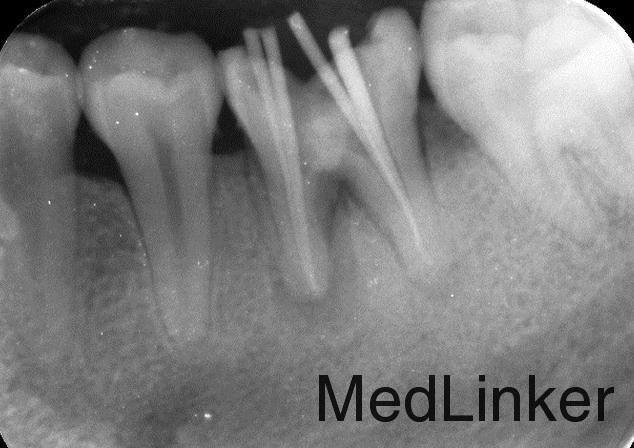

根管治疗加高嵌体修复